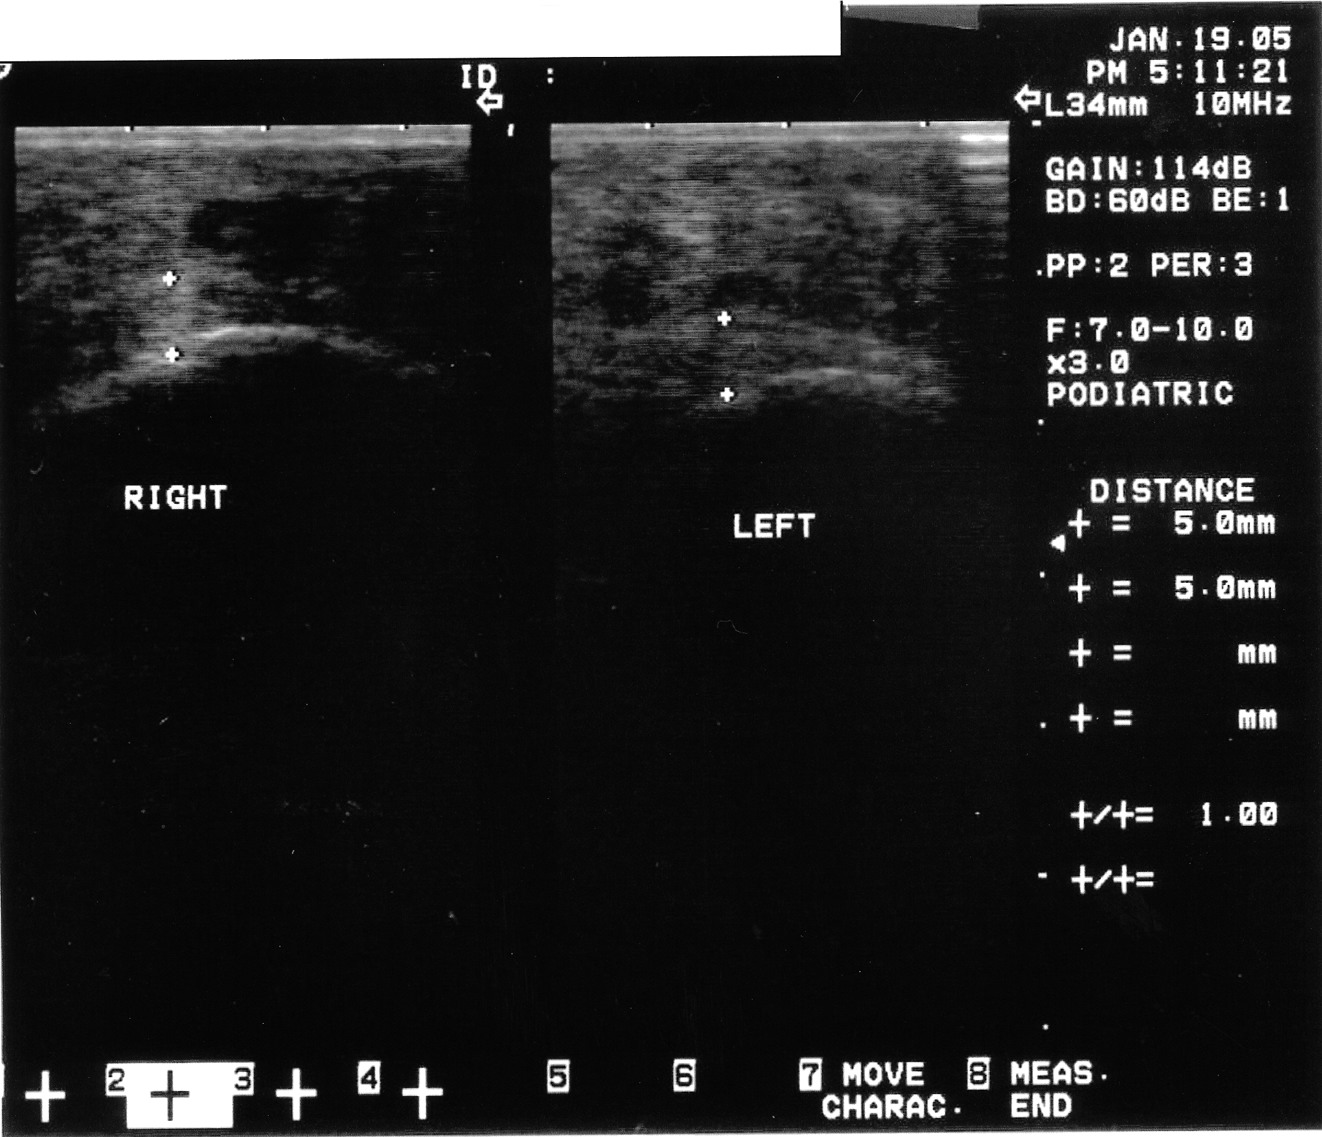

Podiatrists are the experts in dealing with pathology of the heel. It remains one of the leading pathologies that we see clinically. It is also an anatomic area that is easy to ultrasound. While it has been one of the first areas that clinicians new to ultrasound use the device for, I believe this modality is underutilized overall. Granted, podiatrists can diagnose plantar fasciosis clinically with a high degree of accuracy without the aid of ultrasound. However, there are other causes of heel pain that can mimic plantar fasciosis. These possible causes include tarsal tunnel, nerve entrapment, sciatica, soft tissue masses, calcaneal stress fractures and systemic causes. Recently, I had two cases that illustrate this. Case study one. A 52-year-old female presented with heel pain of three months’ duration. The pain was at the inferior aspect of the heel at the medial tuberosity. She noted the pain was worse in the morning and after any period of rest. She had one steroid injection several weeks prior by a podiatrist and was 30 percent better. The clinical exam revealed pain with palpation at the medial tuberosity and central inferior aspect of the calcaneus. The rest of the exam was unremarkable. Radiographs were unremarkable. However, musculoskeletal ultrasound imaging showed indeed that the fascia was thickened but also revealed a well-formed cyst at the inferior aspect of the heel. This was not discernible clinically. Case study two. A 48-year-old male patient presented with a two-year history of plantar fasciosis. Past treatment included seven steroid injections, nonsteroidal antiinflammatories, physical therapy, a night brace, orthoses and two surgical procedures. The improvement was minimal. Subsequent imaging via musculoskeletal ultrasound showed a normal fascia as compared to the asymptomatic contralateral heel. A subsequent assessment revealed the patient had multiple nerve compression.

By utilizing musculoskeletal ultrasound imaging, the clinician can avoid frustration by identifying these esoteric etiologies earlier. One can also assess the severity of the problem. Indeed, clinicians can obtain quantitative measurements of the fascia and make (and document) qualitative assessments. Podiatrists can develop protocols and tailor treatment according to the severity of the condition. The more accurate assessment can help determine the success or lack thereof of the treatment plan that clinicians employ. One can scan the heel with the patient supine or prone. The preferred method is to have the patient in the prone position. Most clinicians lean toward this position because it tends to be easier for the examiner. Assess all three bands: medial, central and lateral. The examiner can scan in the long axis (sagittal plane) and the short axis (coronal plane). By far, the long axis will give the best information on the status of the fascia. One should assess the quality of the fascia. A normal fascia will have a fibrillar pattern. There will be anisotropy present where the fibers attach to the inferior aspect of the calcaneus. Take care not to confuse this with pathology. When documenting this properly, it is important to include a photo with the written description. Assessment then proceeds with measurement of the plantar fascia. Measure at the inferior aspect of the heel. Place the digital calipers at the hyperechoic line that represents the inferior aspect of the heel and the hyperechoic outline of the fascia at its most plantar expansion. (Just to clarify, the superior aspect of the image on the screen represents the plantar aspect of the heel. In other words, the image is inverted. By U.S. convention, the right of the screen should represent distal and the left of the screen would be proximal. Turning the probe 180 degrees will correct the orientation if one finds this not to be the case.) A fascial thickness of 4 mm has been mentioned as the upper limit of normal. When it comes to fascial thickness, I have even heard that one should consider upper normal limits of 4 mm for the medial band, 3 mm for the central band and 2 mm for the lateral band. Barrett, et. al., have looked at cadavers and plantar fascial thickness.1 It stands to reason that fascial thickness will vary depending on the size of the individual. I have seen this in my own practice. I have measured a patient’s normal fascia at 5 mm in thickness numerous times. Accordingly, when it comes to a unilateral case, one must compare the affected heel to the contralateral side. Another pitfall to avoid is including the deep musculature (i.e. flexor digitorum brevis) in one’s measurement. In some individuals, the muscular layer can be delineated deep to the fascia at the heel. Documentation of an ultrasound of the heel can be in a separate report or as a subset of the objective part of one’s notes. Either way, photos should accompany the written report. The assessment should include the measurements of all three bands of the symptomatic fascia and, in a unilateral case, the asymptomatic heel as a comparison. Along with the quantitative assessment, one should include a qualitative description as well and utilize proper terminology. Here are some of the more common terms: • Hyperechoic: increased echo or brightness on the screen • Hypoechoic: decreased echo or gray to dark on the screen • Anechoic: lack of echo or black on the screen • Fibrillar pattern: normal fiber pattern of tendon or ligament • Echotexture: general term referring to the internal architecture of the structure and the echo pattern seen